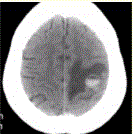

问题 患者女,55岁,右侧肢体无力3d。头颅CT显示如下图。 可能的诊断为(提示进一步询问病史,患者无血液系统病史,并行胸部CT检查,发现肺部肿块(下图)。)

选项 A.急性脑血肿 B.肺癌脑转移瘤伴出血 C.胶质瘤伴出血 D.少枝胶质细胞瘤伴出血 E.血液系统病变伴脑出血 F.脑脓肿 G.血管畸形伴出血

答案 B